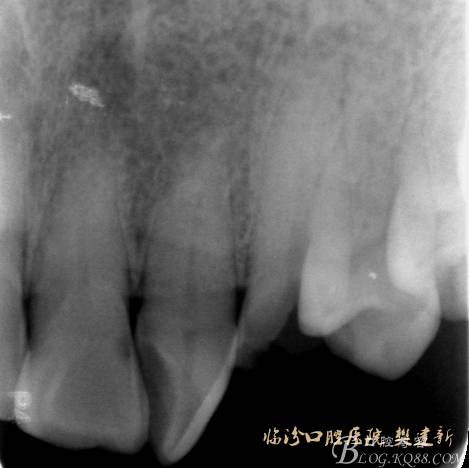

圖2   治療前X片:  23殘根,根尖區(qū)骨密度降低.

640 (1).jpg

圖3   根管治療后X片

640 (2).jpg